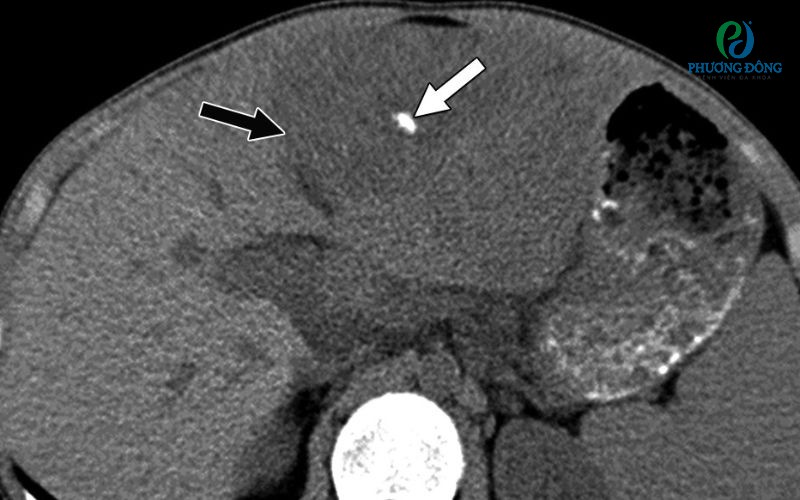

Vôi hóa nhu mô gan xảy ra khi các tế bào gan bị tổn thương bởi các tác nhân như ký sinh trùng, vi khuẩn, virus hay độc chất trong thực phẩm và thuốc. Khi gan phản ứng lại các tác nhân gây hại, vùng nhu mô tổn thương được thay thế bằng mô xơ và mô sẹo. Trên hình ảnh siêu âm, các mô sẹo này xuất hiện dưới dạng những nốt vôi hóa có kích thước khác nhau.

Thông thường, các nốt vôi hóa nhỏ không gây ra biểu hiện rõ rệt. Tuy nhiên, nếu các nốt này phát triển lớn hơn, người bệnh có thể cảm thấy đau tức vùng gan hoặc gặp tình trạng tắc mật do chèn ép đường dẫn mật.